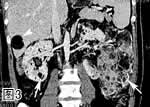

图3. 增强CT冠状位多层面重组像,示双肾巨大肿物,密度不均,可见多发脂肪密度灶(箭号)。肝内亦见一脂肪密度灶(箭头)。